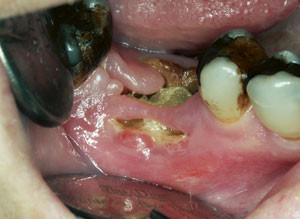

Det er velkjent at bisfosfonater er meget effektive i å redusere symptomer og komplikasjoner ved metastatisk beinsykdom hos pasienter med brystkreft, prostatakreft og multiple myelomer (20). Imidlertid er det i den senere tid rapportert osteonekrose i kjevene (avaskulær beinnekrose) som mulig komplikasjon/bivirkning i forbindelse med slik bisfosfonatterapi (21, 22). De fleste rapporterte tilfeller er assosiert med de høypotente bisfosfonatene pamidronsyre og zoledronsyre og ekstraksjon av tenner under slik behandling (fig 2). Av 36 tilfeller av osteonekrose var 28 (78 %) initiert av tannekstraksjoner (21). Av de resterende «spontane» beineksponeringene synes tynn munnslimhinne å ha betydning, da de fleste tilfellene oppstod på lingualsiden posteriort i mandibelen, et sted med tynn mucosa. Vi har hittil registrert fem tilfeller av bisfosfonatassosiert ostenekrose, alle i underkjeven, fire etter tannekstraksjoner og ett etter oralkirurgisk inngrep.